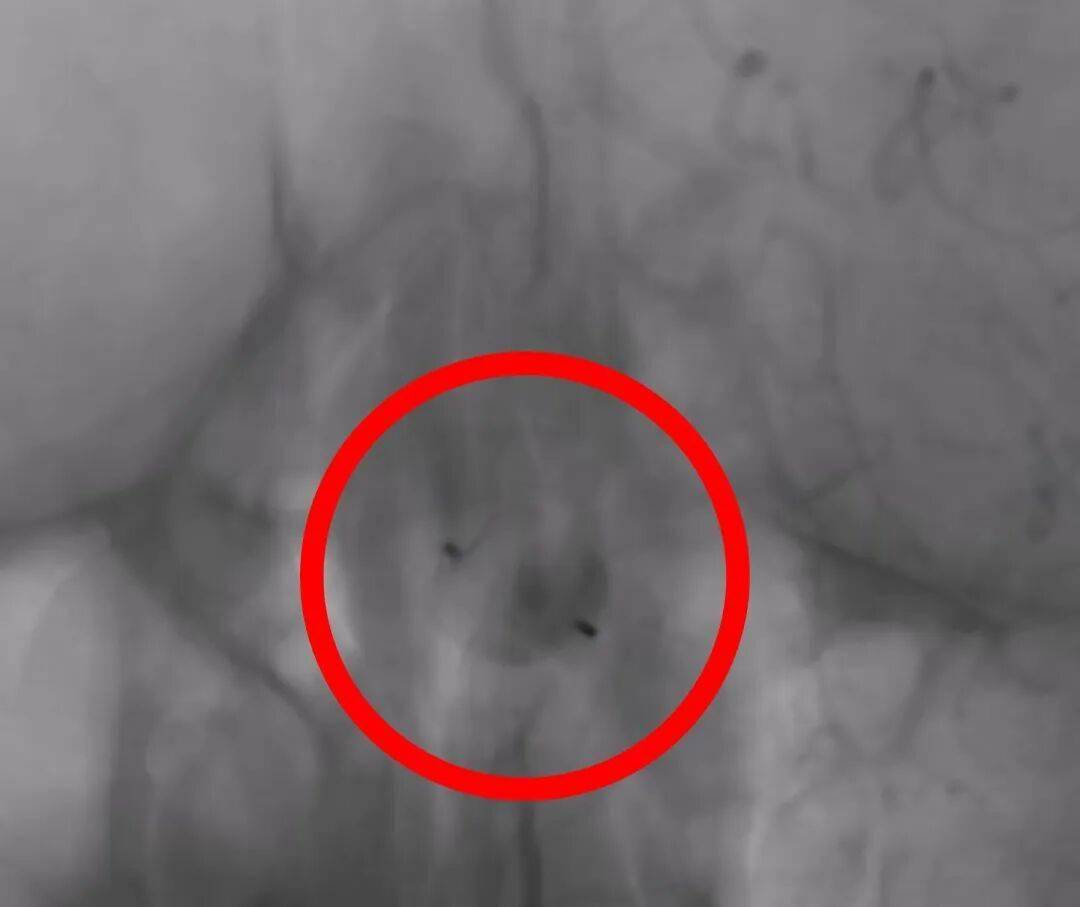

图5-7:扰流装置释放过程、释放结束、术后造影

术后造影显示:装置位置理想,动脉瘤内的血流动力学发生了预期的有利改变,而所有正常的脑血流未受影响。手术取得了圆满成功。